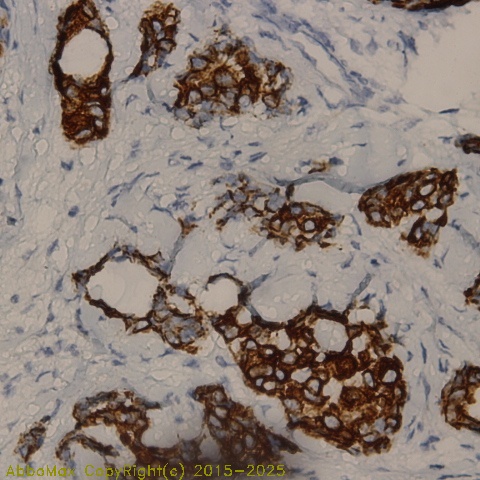

IHC

2-10 µg/ml

Applications: IHC(P), WB